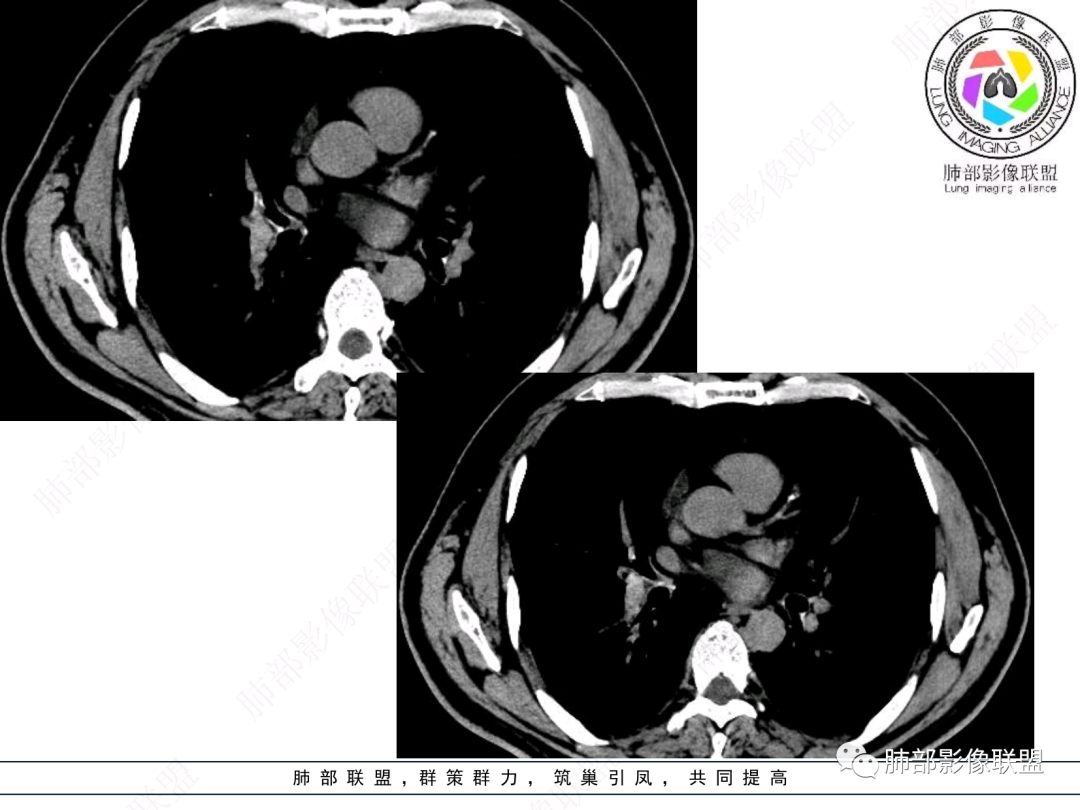

右肺上叶支气管截断,内见软组织密度结节,支气管管壁破坏,病变侵及管外,增强强化明显。右肺上叶沿气管血管束多发斑片影,考虑恶性性病变并阻塞性炎症,鳞癌,神经内分泌肿瘤。

右肺门病灶,支气管腔内堵塞,见有多处低密度影,支气管镜下凹凸不平,直观下不像鳞癌,恶性肯定的,考虑腺样囊性癌可能。

右肺主支气管-上叶支气管腔内结节伴钙化,轻度强化,考虑类癌,鉴别错构瘤与结核。

老年男性,咳嗽咳痰,右肺门增大,右主支气管开口见高密度影,密度不均匀,轻度强化,右肺上叶见多发腺泡结节,支气管管壁增厚,近端粘液栓,支气管镜检查见新生物,考虑鳞癌,鉴别结核。

右主支气管及肺门不规则软组织结节,点状钙化,不均匀强化,气管壁破坏,上叶支气管阻塞,分支粘液栓,血管束增粗,沿支气管分布多发结节,考虑鳞癌合并阻塞性炎症,鉴别结核。

ZhaoXRay:

男性,52岁,右侧主支气管腔内外占位伴点状钙化,病灶大部分位于腔外,右肺上叶散在结节影,气管腔内病灶,动脉期中度强化,静脉期强化减低,首先考虑气管腔内类癌可能,鉴别鳞癌,肺内病变倾向感染性病变;再有气管结核伴肺内播散。

流心明智:

男,52。间断咳嗽、咳痰2周,加重3天。胸部CT:右主、右上叶支气管多发软组织影,跳跃不连续,内可见小环状高密度,点状钙化,管壁破坏,上叶支气管堵塞,远端分支粘液栓,可见小支气管管壁增厚、管腔狭窄,沿支气管分布多发结节,无大片炎症不张。考虑:TB?NTM?鉴别Ca并阻塞性炎症。

这个病例比较好,我们的观察点在哪?这是右上叶支气管病变,需要了解:腔内、壁、腔外、远端,腔内有软组织密度影,近端膨隆。

红色:软骨连续性良好,壁外有软组织密度影,绿色:软骨不连续,破坏了,外面软组织密度影。

南边:提示软骨破坏,也就是病灶腔内朝壁外侵犯了——恶性。

远端支气管腔内不强化的是粘液栓,强化的是肿瘤。

影像上分析的观察点:腔内、壁、腔外、远端,然后就是远端肺组织、淋巴结、肺血管、胸膜、其他肺部,这个人就是阻塞性炎症为主。